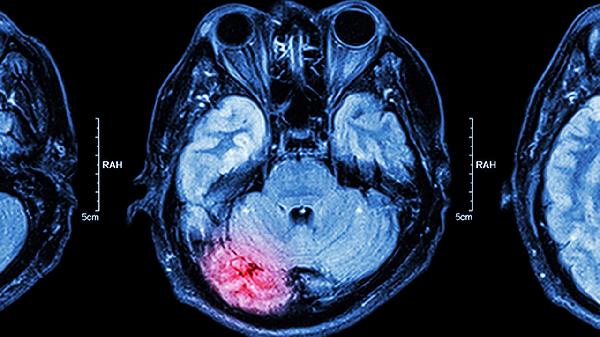

中耳炎、鼻窦炎等颅骨周围感染可能直接侵蚀骨质或经静脉逆行传播。耳源性脑脓肿多由慢性中耳炎引发,伴随头痛呕吐和局灶神经体征,CT检查可见环形强化病灶,治疗需联合耳科手术和抗厌氧菌药物。